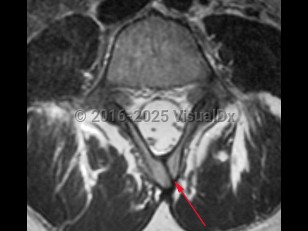

NTDs are classified as open (neural tissue exposed; anencephaly, myelomeningocele, meningocele) or closed (skin covering the defect; spina bifida occulta). Spina bifida occulta, also known as closed spinal dysraphism, is the least severe of the NTDs and results from the incomplete fusion of the posterior vertebral bodies, typically in the lumbosacral spine. Here we will focus on spina bifida occulta.

Spina bifida occulta may be suspected due to the presence of cutaneous lesions such as a dermal sinus tract, sacral dimple, hypertrichosis, hemangiomas, or a subcutaneous lipoma. Cases of spina bifida occulta can present at any age, and the severity of symptoms varies from asymptomatic to severe neurologic impairment due to tethered cord syndrome, secondary to abnormal tension on the spinal cord. Signs and symptoms of tethered cord syndrome secondary to spina bifida occulta include gait changes, bowel / bladder dysfunction, leg and back pain, and orthopedic deformities.